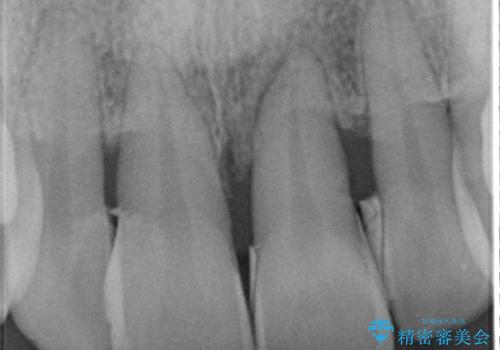

侵襲性歯周炎。前歯の歯周補綴

- 前歯がグラグラすることを主訴に来院されました。

再生治療後、歯周補綴を行っております。

歯周病が進行してしまった歯に対し、再生治療および歯周補綴を行うことで歯周組織の安定を得ることができました。